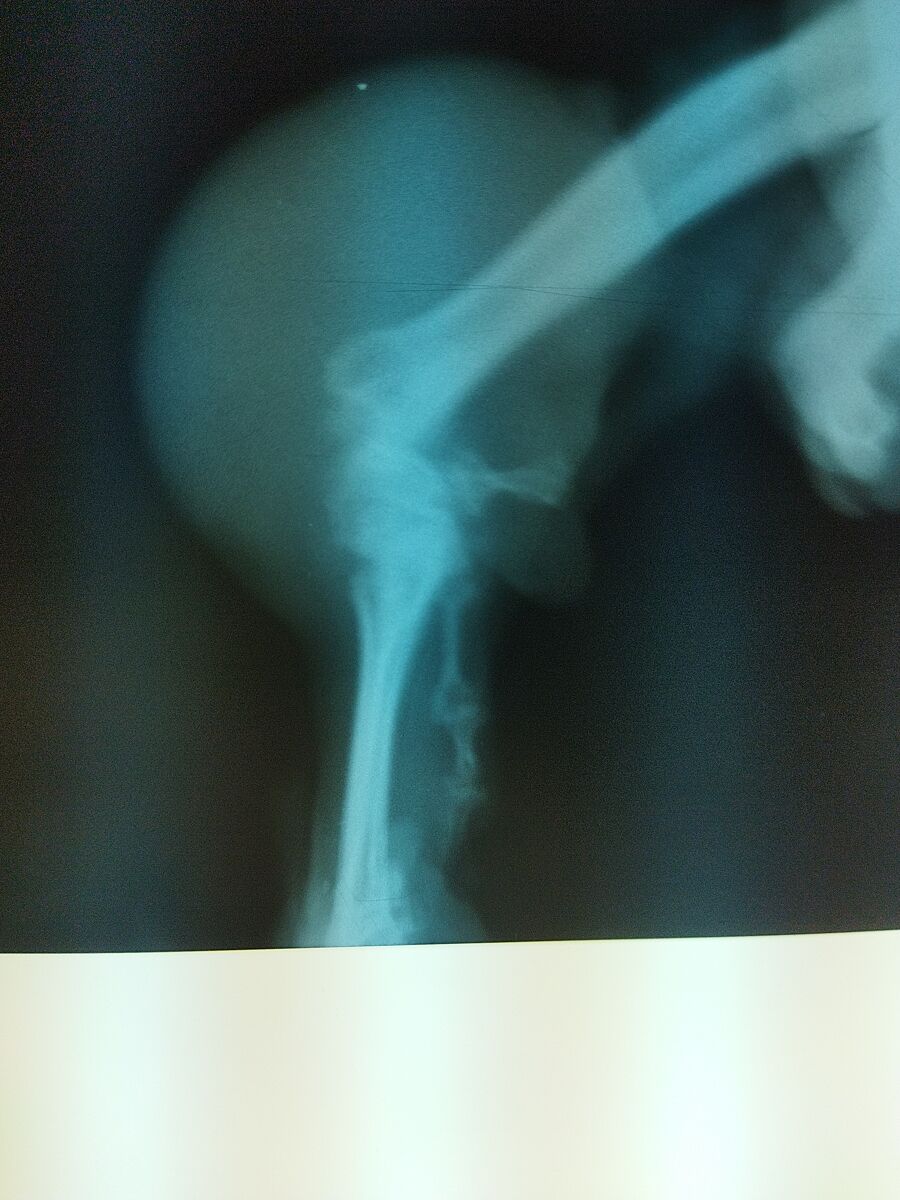

Маємо: звичайна приютівська собака, вік майже 4 роки. У віці 3 міс був перелом тазового відділу хребта, рахіт, не засвоєння кальцію. Шансів не давали. Витягли, лікування дозволило вирости, але він отримав лапи- "плавця", спирається на ліву передню лапу, КІСТЬ правої передньої лапи і ліву задню. Таким чином пересувається досить жваво. Вага зараз близько 12-15 кг.

Кість, на яку він спирається, травмована. Він просто під своєю вагою розбив суглоб. Почала набиратися рідина. Бурсит. Лікували і пункцією, і мазями, і гормоном, і уколами в суглоб курсами. 2-3 місяця лікуємось- 2-4 місяця все гаразд, потім все знову.